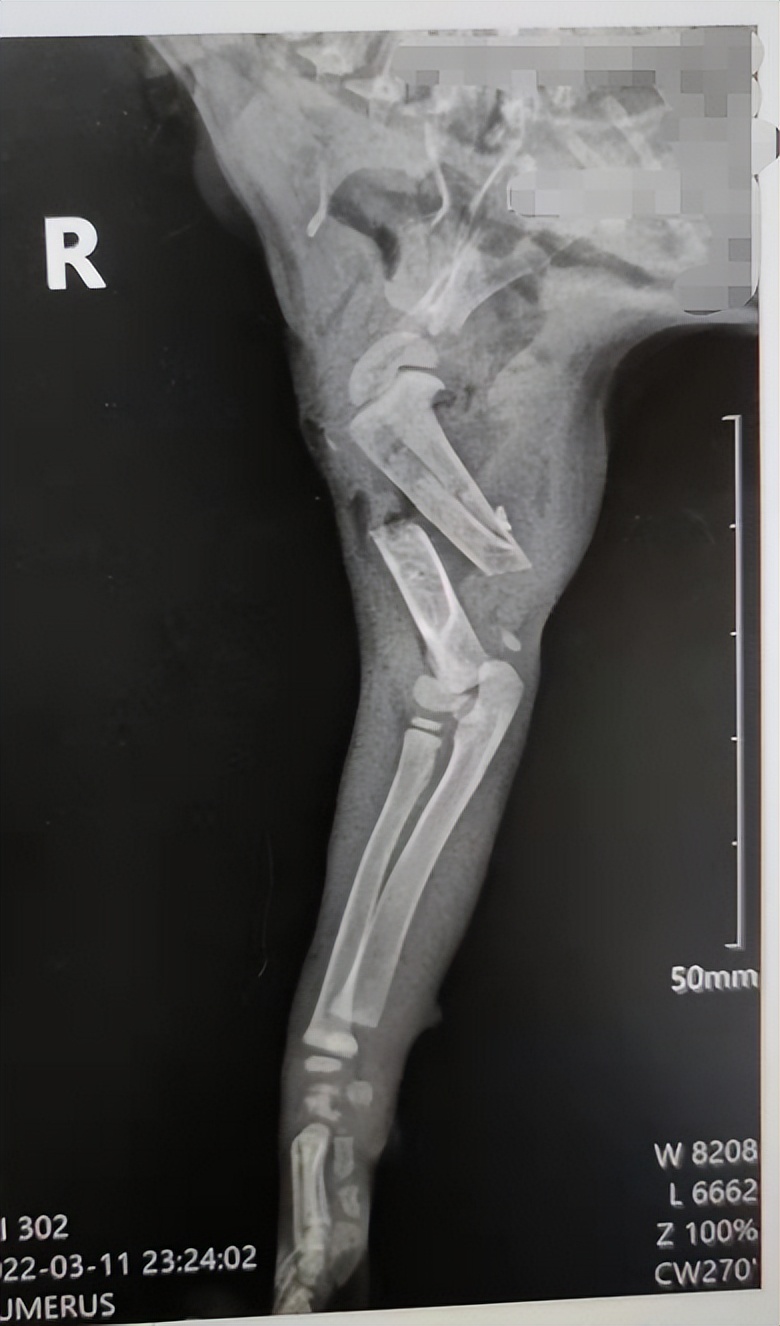

宠物基本情况: 宠物医生您好,一个月的小流浪猫猫被野猫咬伤,右肩胛骨伤口处有牙咬的洞,右手臂骨折了(图2),现在伤口化脓发炎,医生说白细胞少,小爪子黑了。真的不想他被截肢,他太小了,太受苦,求问医生这种伤口化脓应该怎么办啊,伤口化脓发炎应该怎么处理,怎么才能治好他的手,救救他!!!患病时长:四天;用药状况:目前在清洗伤口,想请问医生这种情况要包扎吗?

宠物医生回复: 家长您好,感谢您对友阳宠医的信任!您好,感谢您的耐心等待。 目前通过血常规发现炎症并且有贫血的情况。X光发现骨折,并且肌肉里面有气体,说明里面是有空腔的。

感染应该是很严重 ,如果不进行截肢手术的情况下,暂时冲洗伤口,然后每天涂抹艾迪创伤膏,是有几率恢复的,伤口恢复差不多了可以进行手术,固定骨头,我在临床接诊过类似病例,最后恢复了,但是我接诊的猫年龄大,抵抗力好,恢复起来相对容易一些,经历了很长时间,并且费用也会很多,在保守治疗最后无效的情况下需要进行截肢手术。